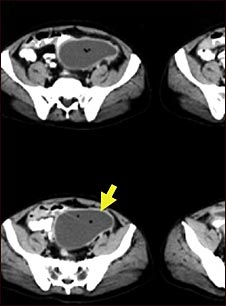

Absceso intraabdominal-TC

TC de la pelvis que muestra una gran masa dentro del abdomen.